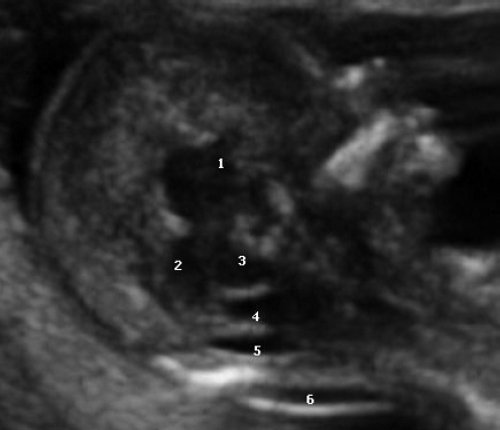

Одним из критериев среднесагиттального корректного скана головного мозга плода в срок 11-14 недель беременности является отсутствие визуализации сосудистого сплетения и скуловой кости верхней челюсти, наличие визуализации кости носа и небного отростка верхней челюсти (рис. 1). Обязательным является наличие на скане диэнцефалона-таламуса (Thalamus), который продолжается в ствол мозга (brain stem), а также чуть ниже в средний мозг (midbrain), с продолжением в интракраниальное пространство, представляющее собой IV желудочек мозга, в котором можно визуализировать гиперэхогенное сосудистое сплетение. Между стенкой IV желудочка и затылочной костью видна анэхогенная большая цистерна головного мозга (cisterna magna). Между затылочной костью и кожей визуализируется воротниковое пространство. Для полноценной оценки структур среднего и заднего мозга необходимо оценить их наличие, размер, взаимоотношение, так как при патологии головного мозга и позвоночника эти критерии меняются.

Рис. 1. Ультразвуковая соноэмбриология структур головного мозга в среднесагиттальном скане в 13 недель беременности.

1 - диэнцефалон;

2 - средний мозг;

3 - ствол мозга;

4 - интракраниальное пространство, или IV желудочек;

5 - большая цистерна;

6 - воротниковое пространство.